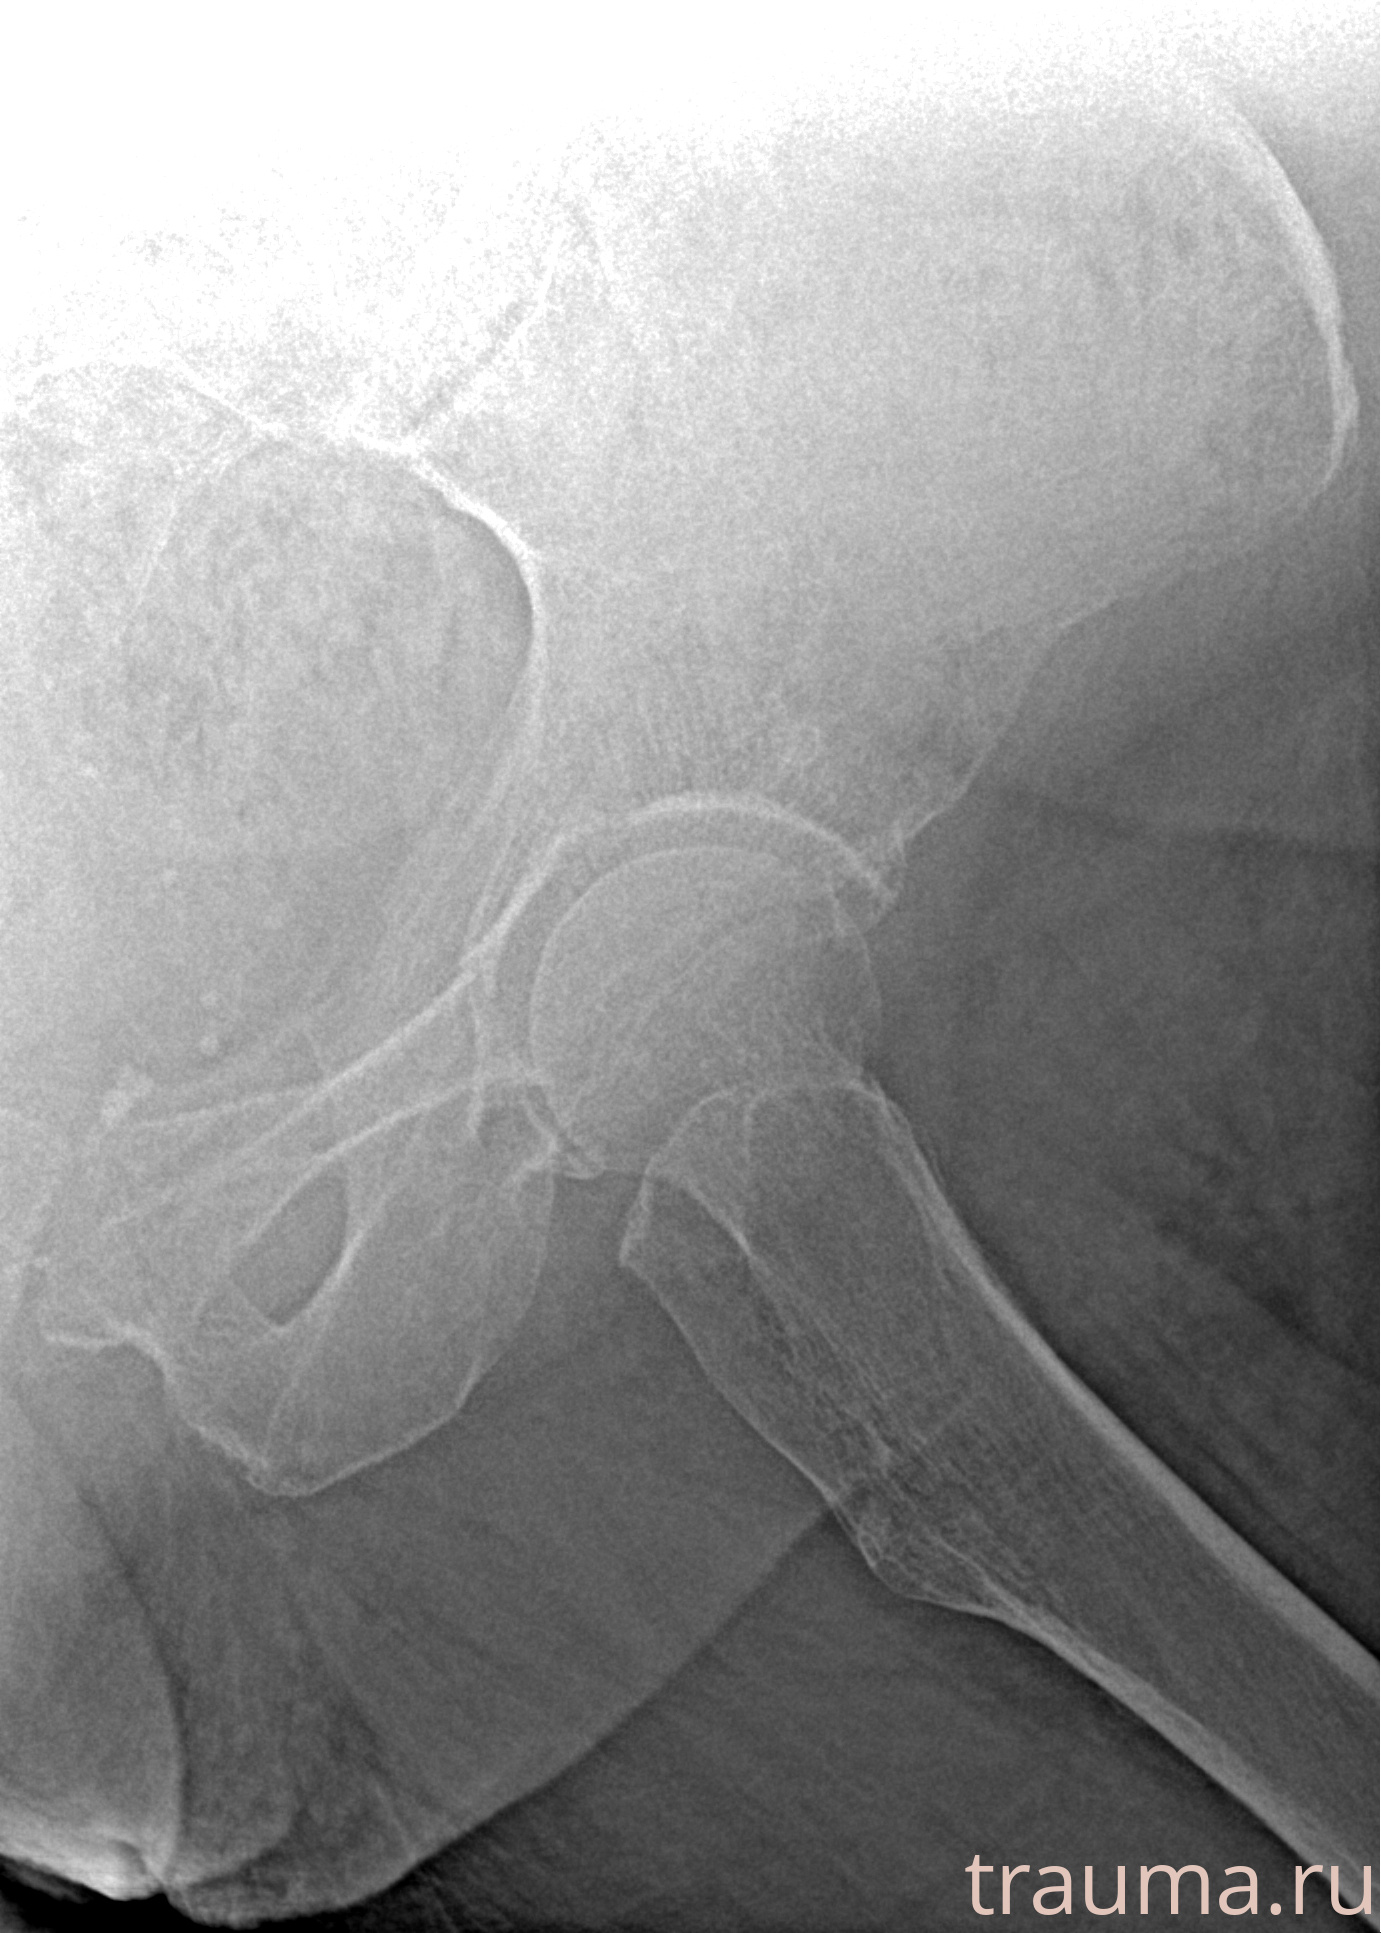

Первая помощь при переломе шейки бедра

Рентгенограммы

Рентген на дому: по вашему адресу приезжает врач-рентгенолог, травматолог-ортопед с мобильным рентгеновским аппаратом, проводит диагностику травмы или заболевания, делает необходимые рентгенограммы, дает рекомендации по дальнейшему лечению. Получить качественные снимки в домашних условиях возможно благодаря уникальной методике, разработанной МосРентген Центром для института  Склифосовского